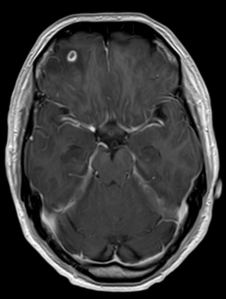

Subsequently, an MRI brain was performed.

In this particular case, the cause of the seizures is almost certainly neurocysticercosis. There are other differentials of course, i.e. central nervous system tuberculoma or meningioma, but they are far less likely.